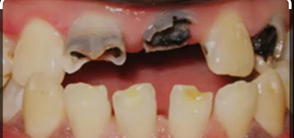

Dental caries

Tooth fully arrested by caries and tooth become un restorable.

દાંત નો સડો

જ્યારે આખો દાંત સડી ગયો હોય અને બચાવી શકાય એવું ન હોય ત્યારે દાંત કાઢવો પડે છે.